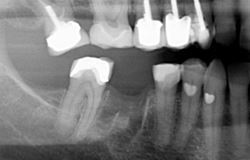

bridge-xray

• bridge-xrayA local anaesthetic may be need to numb the tooth and surrounding gum